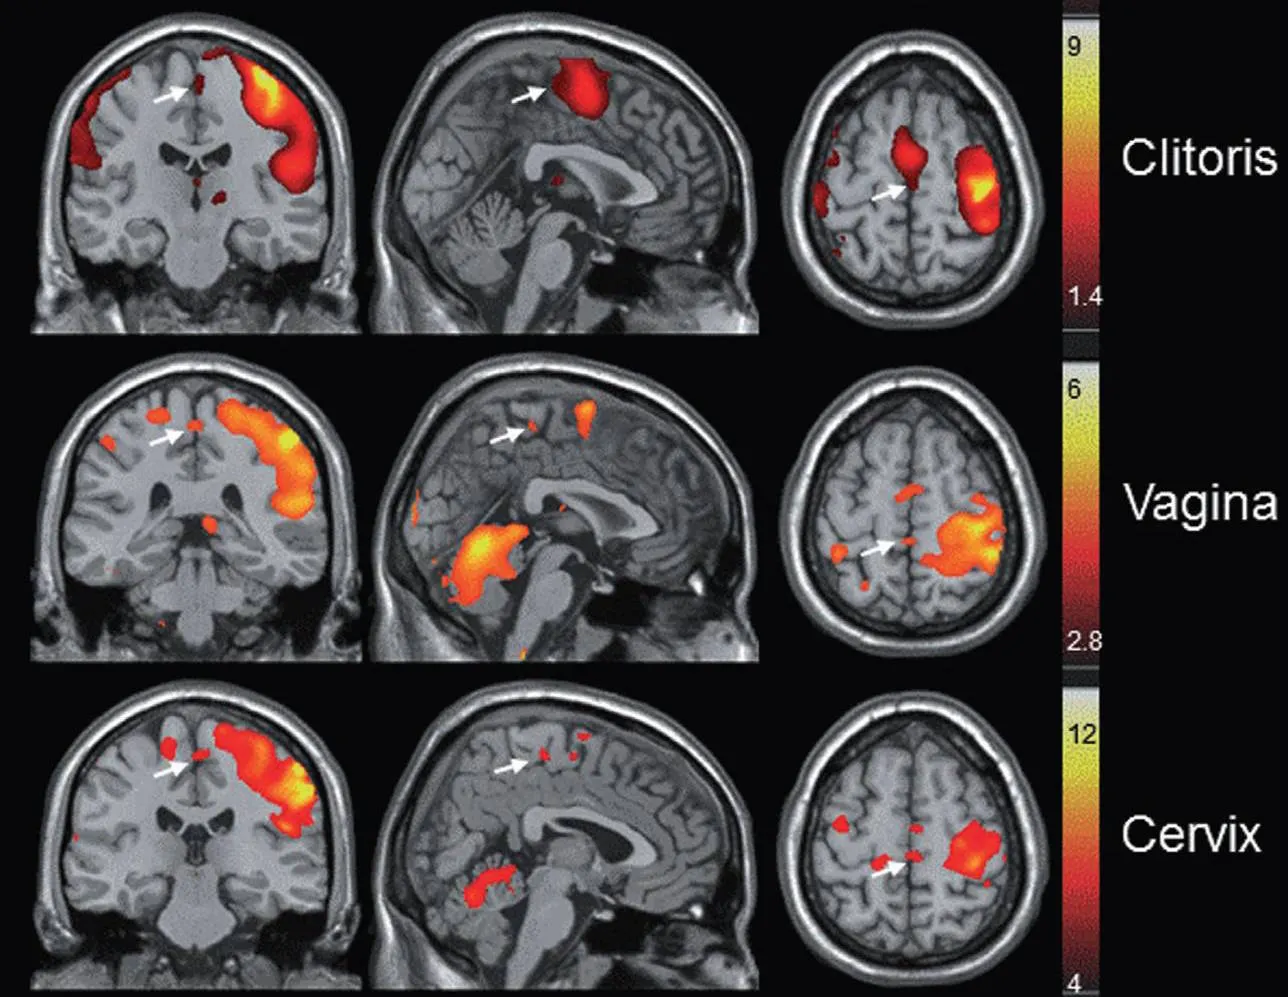

Did you know? When desire disappears—whether from stress, hormonal changes, medications, or just life—the melanocortin receptors in your brain (the ones responsible for sexual desire) become significantly less active.

That's why The Little Pink Pill includes PT-141 (Bremelanotide), an FDA-approved ingredient that:

● Directly activates desire centers in your brain